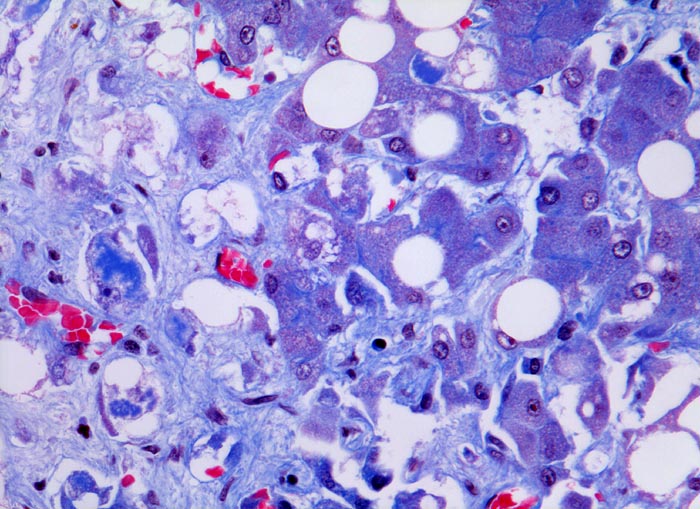

Meist findet sich eine grobtropfige oder gemischttropfige Verfettung des Parenchyms. Schon im Frühstadium der alkoholischen Steatohepatitis kann eine perizelluläre Maschendrahtfibrose, perisinusoidale und perivenuläre Fibrose mit Beginn in der Zone 3 festgestellt werden. Die Kombination von perivenulärer und perizellulärer (> 1096) Fibrose wird bei starker Ausprägung mit Arealen von dichter Kollagenfaserbildung auch als zentrale sklerosierende hyaline Nekrose bezeichnet. Wenn der Vernarbungsprozess fortschreitet, kann die perivenuläre Fibrosezone mit vernarbten Portalfeldern verschmelzen. Zentralvenen verschwinden oder sind stark in der Anzahl reduziert. Eine Phlebosklerose oder Obliteration der Zentralvenen kann hinzukommen. Breite Bänder von fibrotischem Gewebe mit Ductulusproliferationen und gemischtem Entzündungsinfiltrat umgeben die bei alkohlischer Zirrhose meist kleinen Regeneratknoten (=mikronoduläre Leberzirrhose mit Regeneratknoten von weniger als 3mm Durchmesser). Bei längeren Abstinenzphasen kann sich aufgrund der gesteigerten Regeneration auch eine gemischtknotige Zirrhose ausbilden. Ein gleichzeitiges Vorliegen einer Steatose oder Steatohepatitis (Steatose+neutrophile Granulozyten) in einer alkoholischen Leberzirrhose signalisiert in der Regel einen fortgesetzten Aethylabusus. Typisch für alkoholtoxische Leberschädigung sind Mallory-Denk Körperchen (> 3021), Megamitochondrien (> 3022) und eine Zellschwellung (=Ballonierung) aufgrund einer gestörten Albuminausschleusung. Oft können mässige Mengen von Hämosiderinablagerungen vor allem in den Kupffer Zellen nachgewiesen werden. Weitgehend identische morphologische Veränderungen wie bei der aethylischen Leberschädigung finden sich auch bei der nicht alkoholischen Steatohepatitis (NASH) d.h. bei Patienten, die keinen oder nur wenig Alkohol konsumieren.

• Zerstörte Läppchenarchitektur mit diffusem feinknotigem Umbau des Leberparenchyms.

• Breite Fibrosebänder mit Ductulusproliferation und gemischter Entzündung.

• Perivenuläre Fibrose und perizelluläre Maschendrahtfibrose in Zone 3.

• Verminderte Anzahl Zentralvenen.

• Überwiegend makrovesikuläre, teils gemischttropfige Verfettung der Leberzellen.

• Intralobuläre Infiltrate neutrophiler Granulozyten (alkoholische Steatohepatitis: grobtropfige Verfettung, Maschendrahtfibrose und intralobuläre neutrophile Granuloyzten).